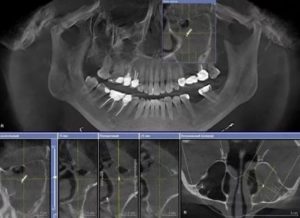

Только на рентген снимке или на экране компьютера при томографии можно обнаружить проблему.

- рентген снимок, который показывает не только наличие тела, но и пневматизацию (наличие воздуха);

- применение компьтерной томографии;

- КТ – обеспечивает самую точную диагностику, позволяет выявить наличие инородного тела и других воспалительных процессов, масштабы поражения слизистой оболочки полости носа и количество гноя.

- Рентгенография верхнечелюстных пазух – на снимках отлично видны все уплотнения, гнойные образования и другие дефекты.В данном случае понадобится также диагностика и консультация врача-хирурга, комплексный осмотр поможет выявить проблему и назначить лечение.

Перед проведением гайморотомии врач направит на комплекс дополнительных исследований:

- рентгенологическое исследование или КТ придаточных пазух;

Практически в 100% случаев точно диагноз позволяет установить КОМПЬЮТЕРНАЯ томография пазух носа. Обычный рентген и МРТ дают менее информативную картину. На результатах компьютерной томографии часто можно четко увидеть и пломбу и формирующееся грибковое тело, как показано на рисунке.